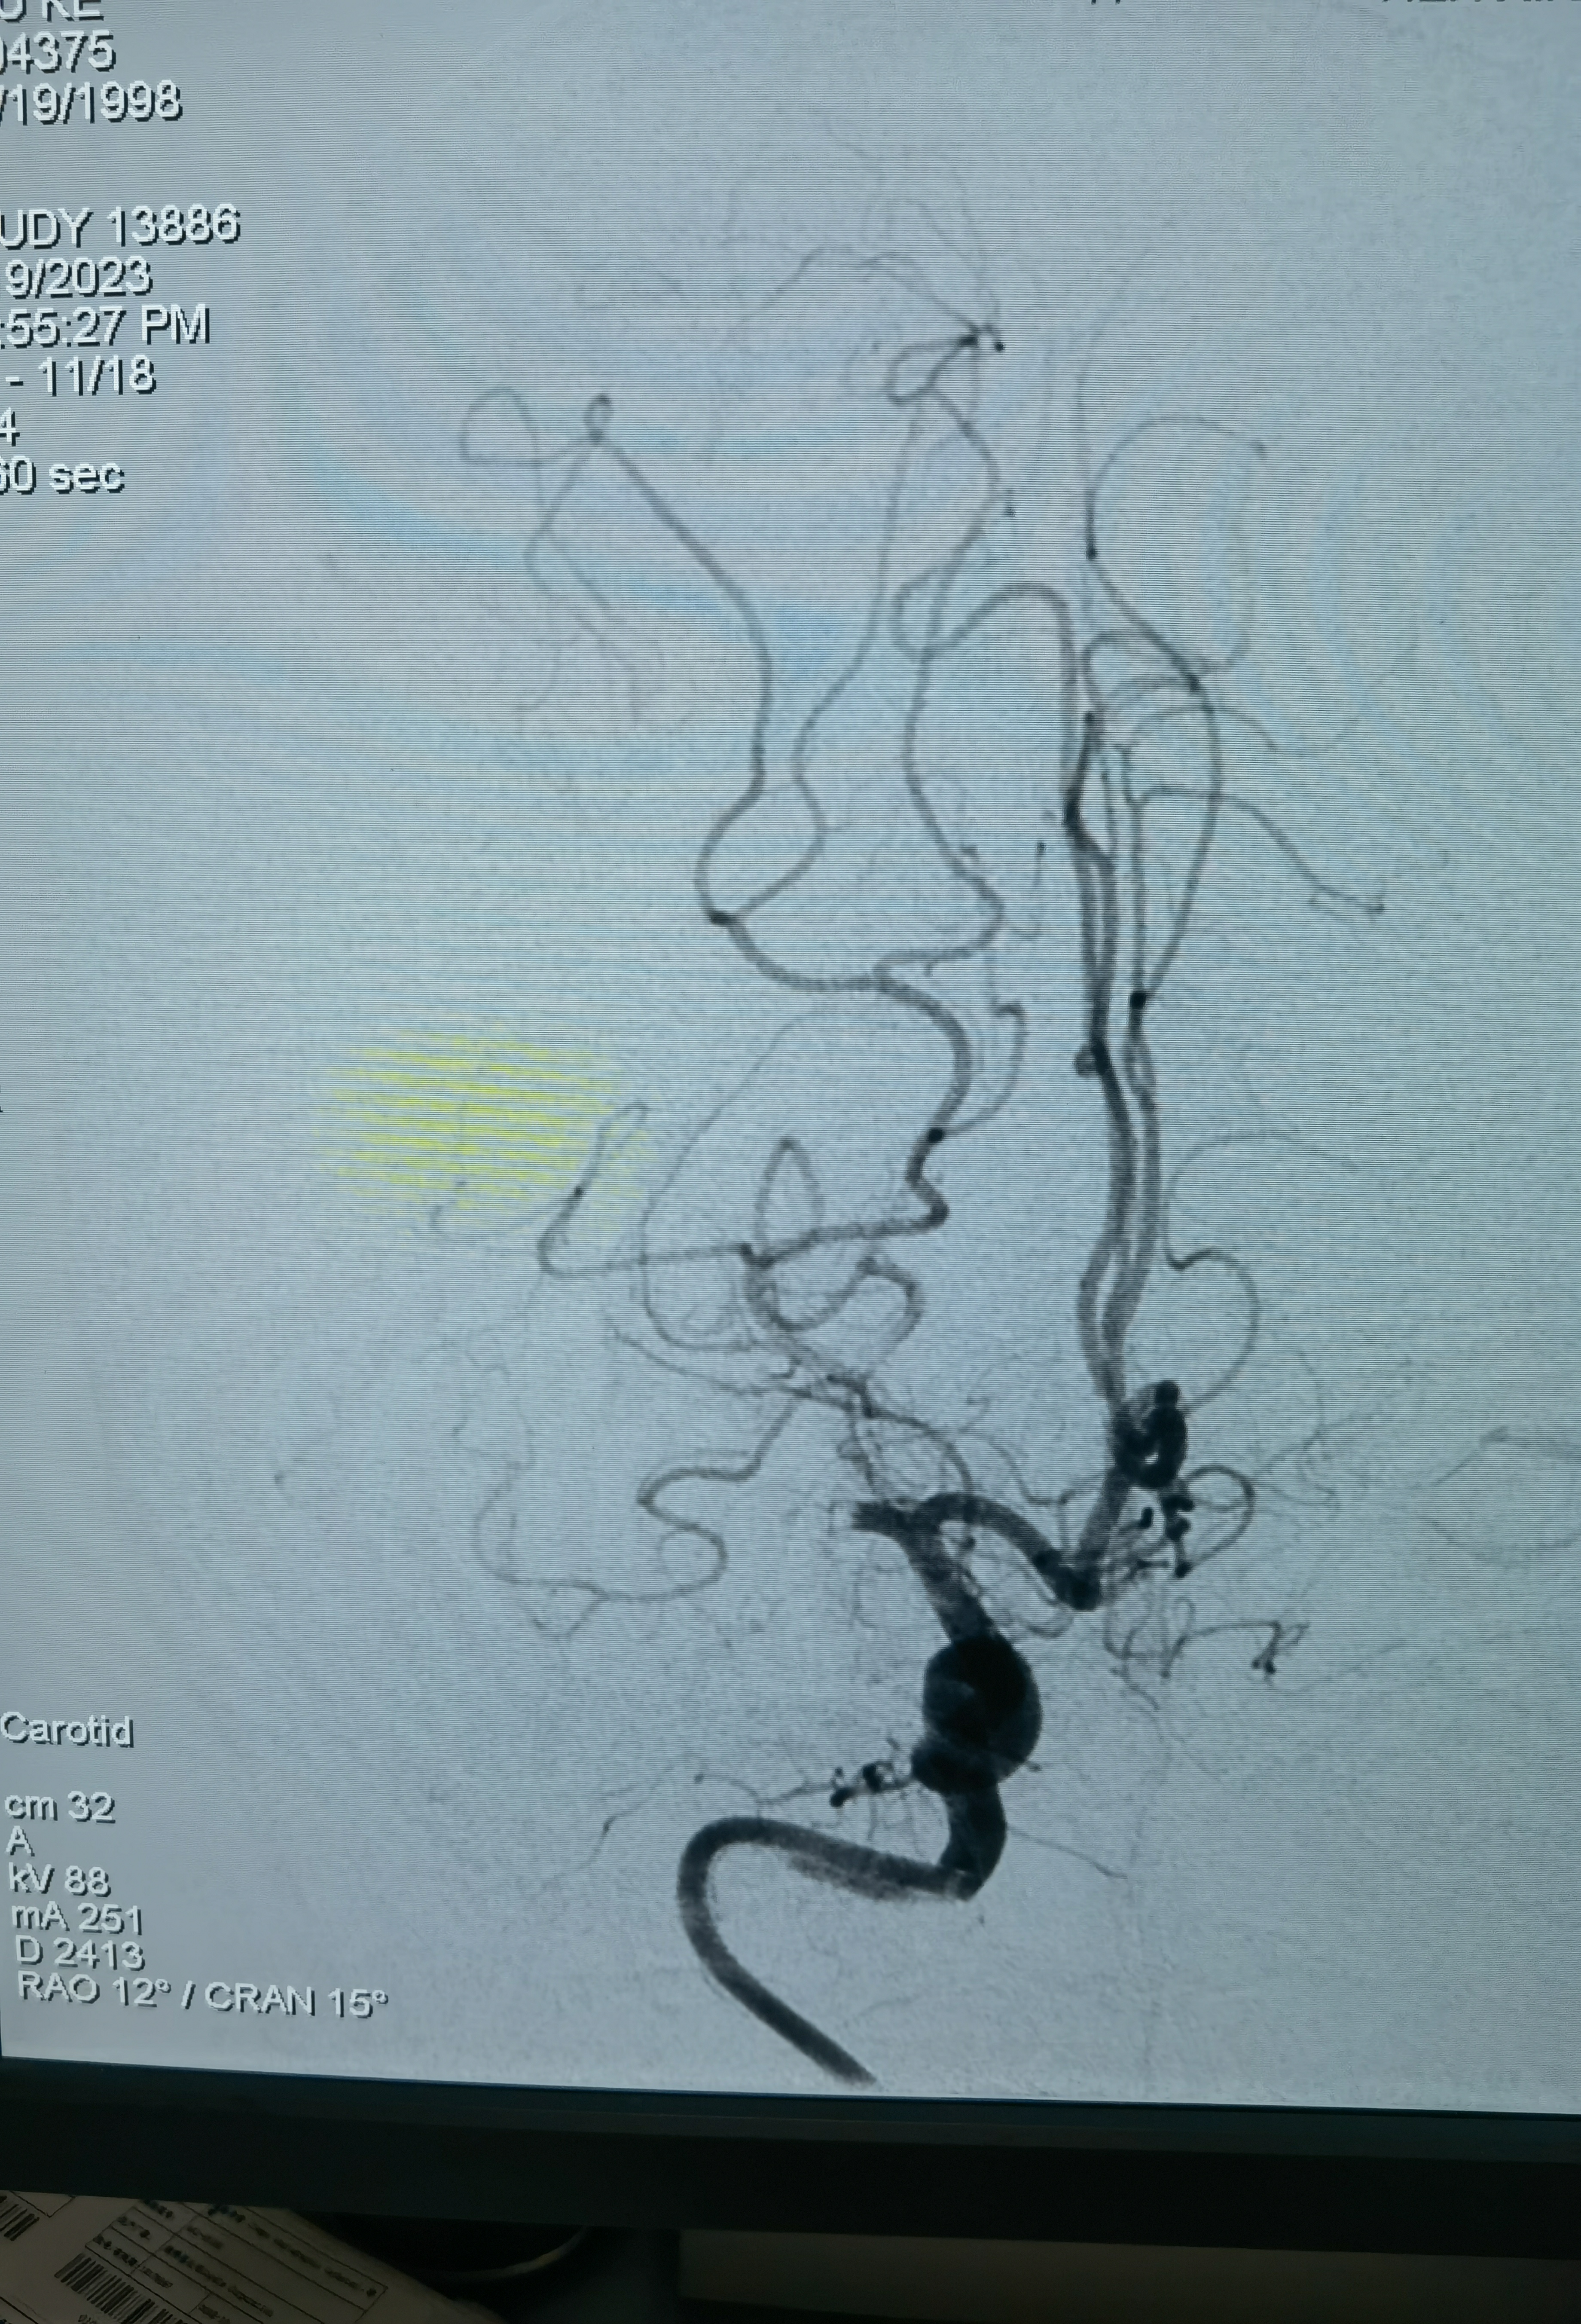

改为右桡动脉入路,桡动脉搏动也弱,考虑大动脉炎可能右上肢血管也受影响了,不过还是穿刺成功,泥鳅导丝带猪尾巴管造影,在腋动脉处通过困难,试了两次还是顺利过去了,弓造影上可以看到右侧锁骨下动脉几乎不显影,肋颈干发出粗大分支血管向右上肢供血,说明锁骨下要么闭塞,要么也是重度狭窄,弓造影结束长泥鳅导丝保留,退出猪尾巴管,交换上SIM造影导管,在弓里成袢后超选右颈总困难,导管被血管抱死,导管软,内衬泥鳅导丝推不动!

换MPD头端放到头臂干右颈总开口处,内衬猪尾巴管,利用猪尾巴管头端的弯儿勾右颈总动脉,猪尾短,截了一节MPD,把泥鳅导丝头端送到右侧颈内动脉,猪尾巴管带到分叉,猪尾巴管造影确认右侧大脑中动脉闭塞!

闭塞血管明确,需要取栓治疗。问题来了!手头没有合适的6F经桡的中间导管,也没有合适的6F长鞘!怎么办?换8F鞘!鞘头进入血管一点,能固定住就行,泥鳅长单弯同轴带8F禾木的导引导管到右侧颈内动脉!

中间再上一禾木6F127抽吸导管,造影